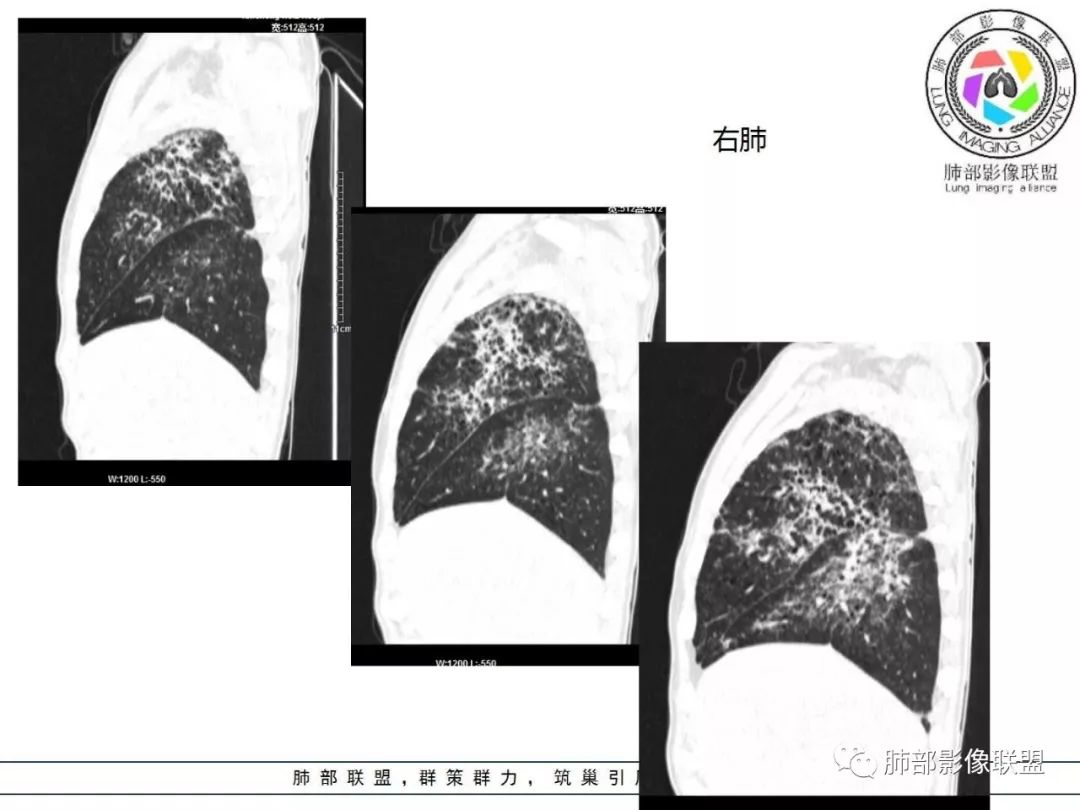

双肺间质性病变,中央间质增厚,胸膜下间质增厚,左侧胸膜肥厚,胸廓变小,肋间隙变窄。

胸部CT:两肺弥漫病灶,磨玻璃影,少许实变,部分累及胸膜,磨玻璃区可见囊?少许胸腔积液,两肺可见结节,支气管血管束增粗,小叶间隔增厚,支气管走形有扭曲扩张,可见纤维化。气肿、大泡。考虑:感染性病变,PCP?查下HIV,CD4,G等。鉴别结核、结缔组织病肺浸润。

患者中年男性,发热1月,体温38℃-39℃,峰值40℃,无畏寒、寒战,伴黄痰,CRP升高明显,降钙素原稍升高,血沉、血糖正常。胸部CT:两肺弥漫病变,磨玻璃影+点片渗出,部分累及胸膜,磨玻璃区边界清楚,少许胸腔积液,两肺支气管血管束增粗,小叶间隔增厚,部分支气管走形有扭曲扩张,可见肺气肿、右肺尖肺大泡及部分纤维化改变。综合考虑:感染性病变。结核或PCP可能性大,鉴别风湿免疫、结缔组织疾病肺浸润和腺癌等恶性病变。

胸部CT:两肺弥漫病灶,中央间质分布为主,部分位于胸膜及叶间裂旁,磨玻璃影,斑片影,部分实性结节,肺气囊,支气管血管束增粗,小叶间隔增厚,叶间裂不均匀增厚,支气管走形有扭曲扩张,可见纤维化、气肿、大泡。考虑:LIP加MALT。鉴别PLCH、PCP、结核、结缔组织病肺浸润。

双肺弥漫性病变,多发磨玻璃密度及小叶间隔增厚,大部分沿支气管血管束分布,伴支气管轻度扩张,以午后及晚上发热为主,考虑感染性病变,间质性结核可能大,另双肺多发肺气囊,LIP待排

病灶呈片状磨玻璃密度影,呈典型的烟花征。磨玻璃影密度偏高,有网结节样改变,与正常肺实质分界清楚,且常见相对高密度的勾画。

病变一般沿血管支气管束分布或小叶分布,一般上肺多于下肺(这与常见继发性肺结核分布相若)。

2. 肺气肿背景(小叶中心性肺气肿);双肺多发病灶整体沿血管支气管束及胸膜下分布,以上叶及下叶背段分布为主,有实变及GGO,边界清楚,有树芽,小叶间隔及中央间质增厚,叶间裂见到多发结节,部分支气管不规则牵拉扩张,提示病灶纤维化明显,结合临床病史,考虑病灶为间质性感染,肺门及纵隔内有钙化淋巴结,小叶间隔结节,考虑淋巴道增值性疾病可能,综合常规要怀疑间质性肺结核。